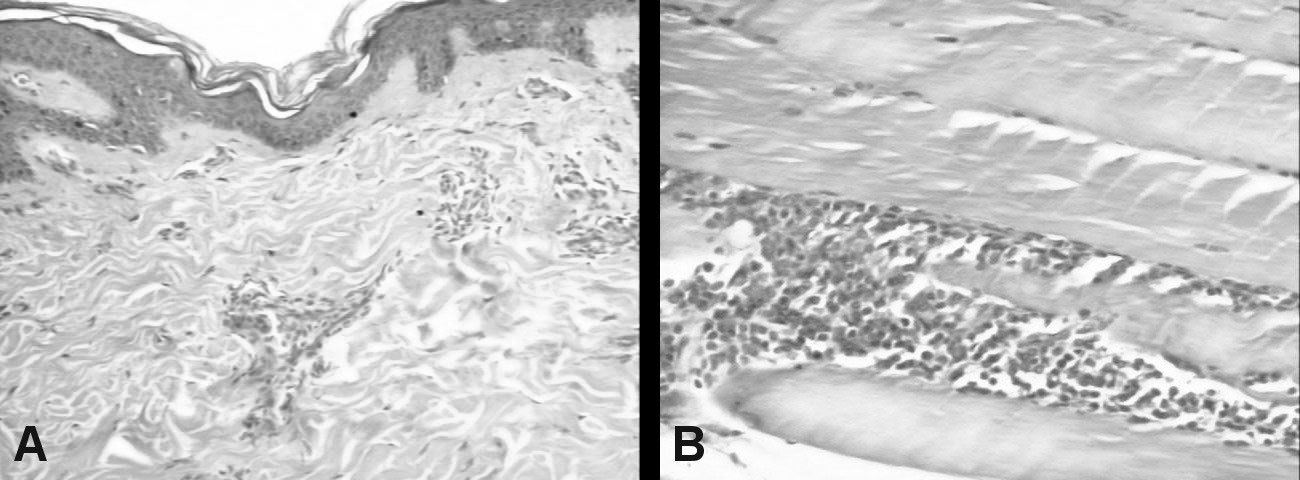

Skin and muscle biopsies are shown in (Figure 2A and Figure 2B). Audiometry: Moderate to severe bilateral neurosensorial hearing loss.

Figure 2: A) Skin biopsy (HE × 100): Mild epidermal lamelar hyperkeratosis. Superficial dermis showing moderate perivascular lymphocytic infliltration; B) Muscle biopsy (HE × 100): Mature adipose tissue, no atypical cells; Skeletal muscle fibers with moderate perimysial lymphocytic infiltrate. View Figure 2

In fact, the first and most prominent feature of this case was the generalized muscle involvement with lower limb predominance. The histopathological examination showed vascular inflammation and lymphocytic infiltrate, which are considered characteristic features of this disorder [4,7].